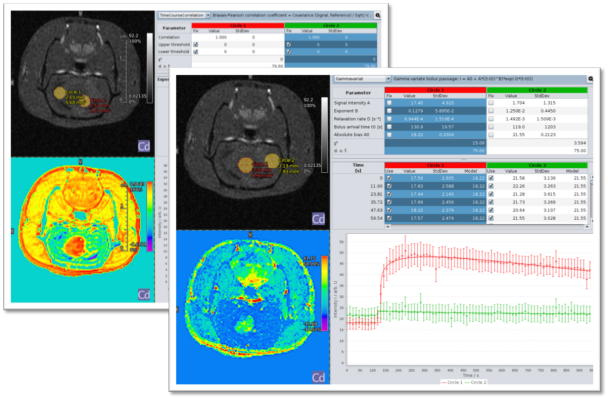

Interactive navigation, including immediate update of parameter map. Image Credit: Bruker BioSpin Group

- On-the-fly quantitative image mapping

- ROIs with thresholding, seeded region growing, and freehand definition

- Kinetic time course image reconstruction and segmentation

- TAC display with Patlak fit for kinetic modeling